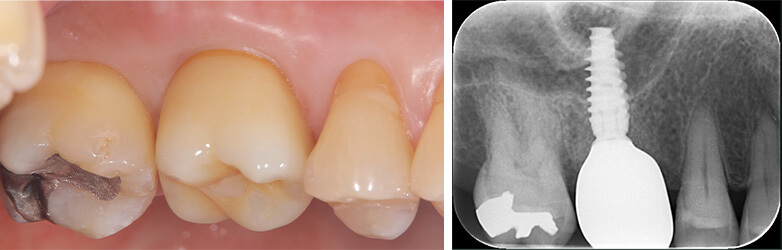

技工士が歯の色に合わせて一つ一つ丁寧にセラミックインレーを製作します。

セラミックインレーの装着時には写真のようにラバーダムというゴムのシートを使うことにより接着力が増します。

接着力が増すと虫歯の再発率を減らすことにつながります。